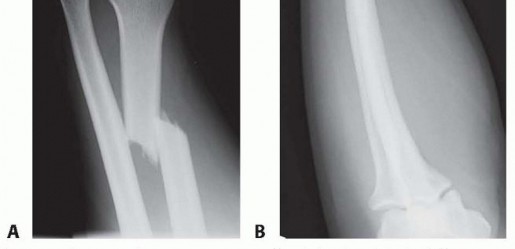

Fracture of the radial shaft with an associated distal radioulnar joint (DRUJ) dislocation (FIG 1A,B) It is well established that anatomic stabilization of the radial shaft fracture typically results in a stable DRUJ that can be treated nonoperatively with a period of immobilization. When the DRUJ is either irreducible or unstable, following anatomic reduction and compression plating of the radius fracture, operative stabilization of the DRUJ is required.

### FIG 1 • Classic Galeazzi injury. A. A distal-third radial shaft fracture with ulnar angulation of the distal fragment, radial shortening, and DRUJ widening. B. Apex dorsal angulation of radial shaft fracture with dorsal dislocation of ulnar head.